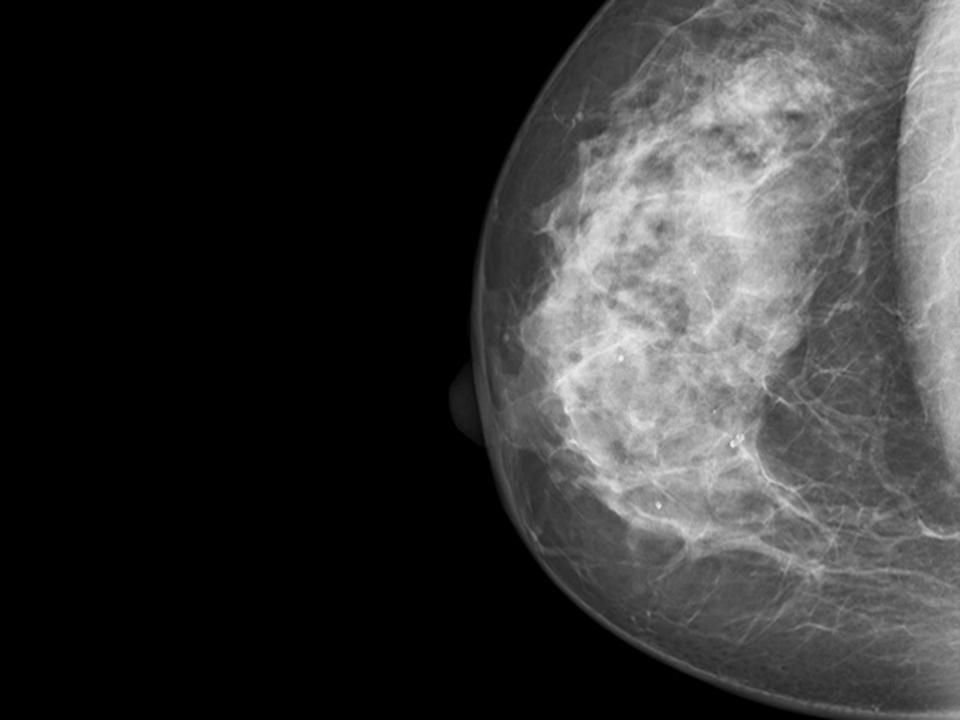

Clear analysis of dense breast tissue